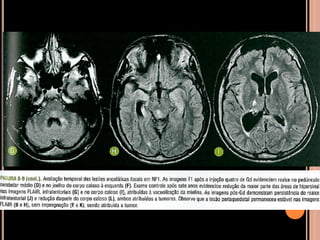

Área de vacuolização de mielina

 Origem é controversa;

 Achado típico em crianças com NF1;

 Focos hiperintensos em T2 e no FLAIR em núcleos

da base, cápsula interna, tronco encefálico e

cerebelo;

 Mais comum no globo pálido, geralmente bilateral;

NF1

Vacuolização de mielina

 Aparecimento geralmente aos 3 anos  aumenta

até os 12 anos  tendência a regredir;

 Raro observar após os 20 anos de idade;